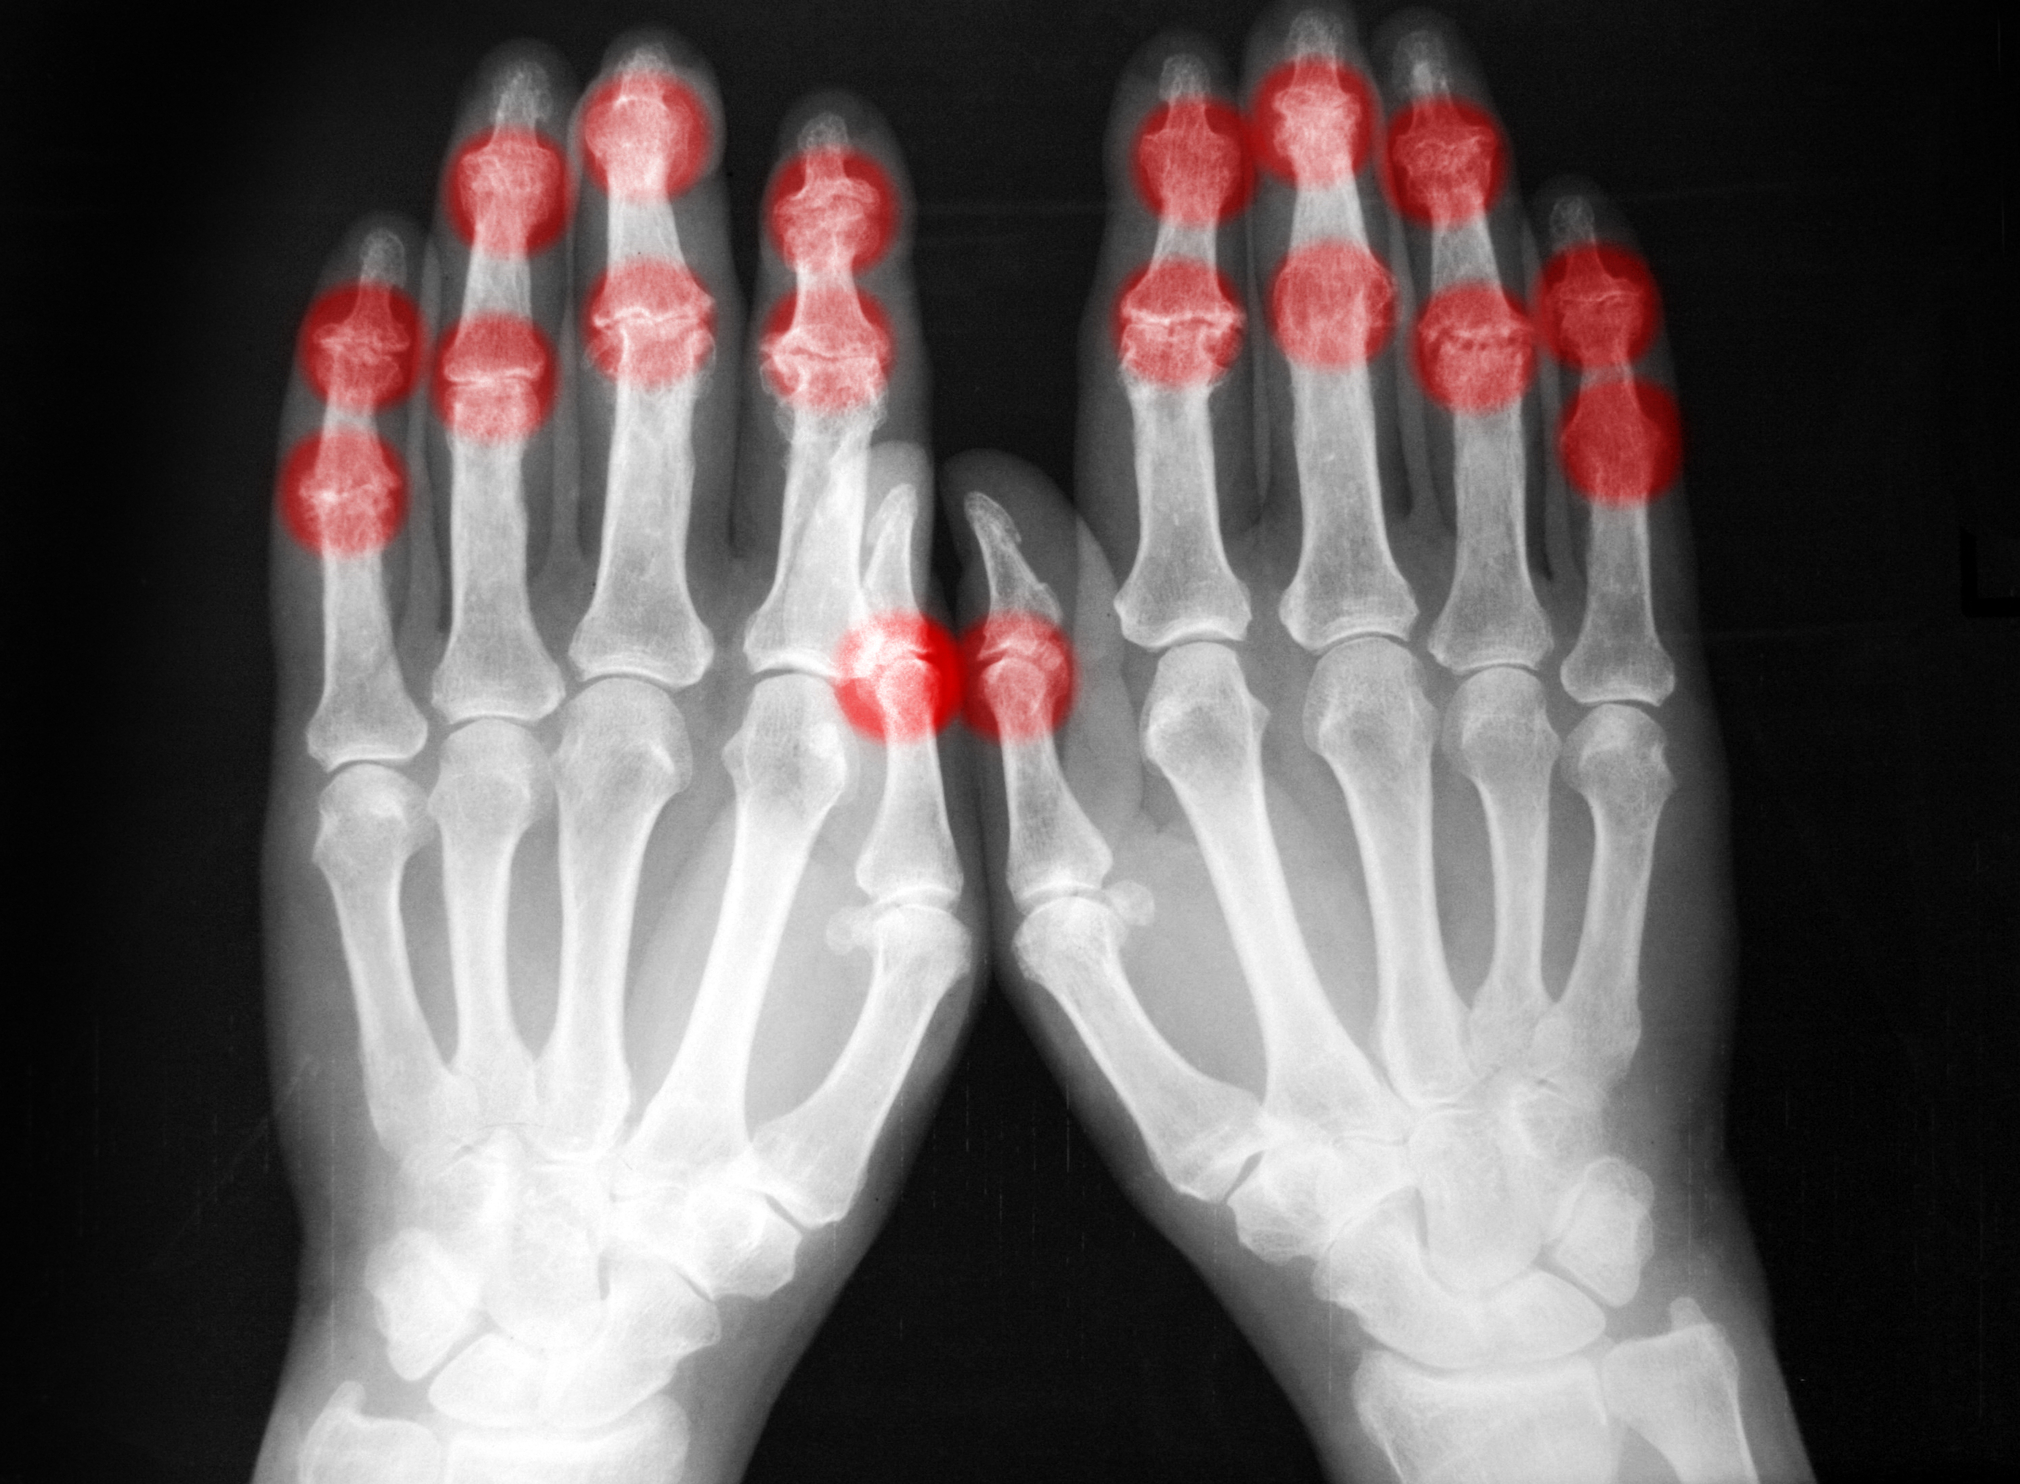

Psoriatični artritis je oblika artritisa, ki spada v skupino spondiloartritisov in prizadene nekatere ljudi s kožno boleznijo, imenovano luskavica (psoriaza). Luskavica povzroča rdeče madeže na koži, ki so prekriti s srebrnimi luskami.

Glavni znaki in simptomi vključujejo bolečine, otrdelost in otekanje sklepov, ki se pojavijo kjerkoli v telesu, vključno s prsti na rokah in hrbtenico.

Bolezen lahko vpliva na sklepe na eni ali obeh straneh telesa. Znaki in simptomi psoriatičnega artritisa pogosto spominjajo na tiste pri revmatoidnem artritisu – vendar je luskavični artritis običajno nesimetričen. Obe bolezni povzročata bolečine, otekanje in občutek toplote in okorelost v sklepih.

Otekanje prstov na rokah in nogah. Bolezen lahko povzroči bolečino in otekanje prstov, ki mu rečemo daktilitis – klobasasti prsti.

Rentgenske slike sklepov lahko pokažejo značilne spremembe, ki dodatno podpirajo diagnozo.